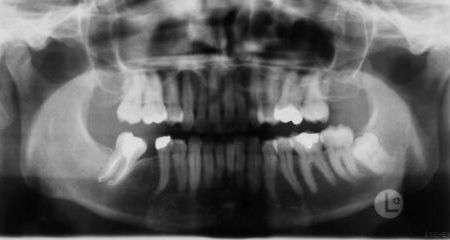

Röntgenbefunde

Links Röntgenbefund vor der Behandlung, rechts Zustand während der Behandlung. Die Lücke im Unterkiefer rechts (linke Seite auf dem Röntgenbild) wurde durch Vorbewegen und Aufrichten des endständigen (wurzelgefüllten) Backenzahnes geschlossen. Prothetische Maßnahmen wurden dadurch überflüssig, außerdem verbesserten sich die Verhältnisse für den Zahnhalteapparat dieses Zahnes deutlich. Der Weisheitszahn im Unterkiefer links wurde vor der chirurgischen Vorverlagerung des Unterkiefers entfernt, um eine ungünstige Trennung der Knochenfragmente zu vermeiden.